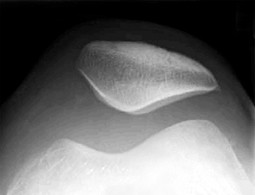

Abb. 3